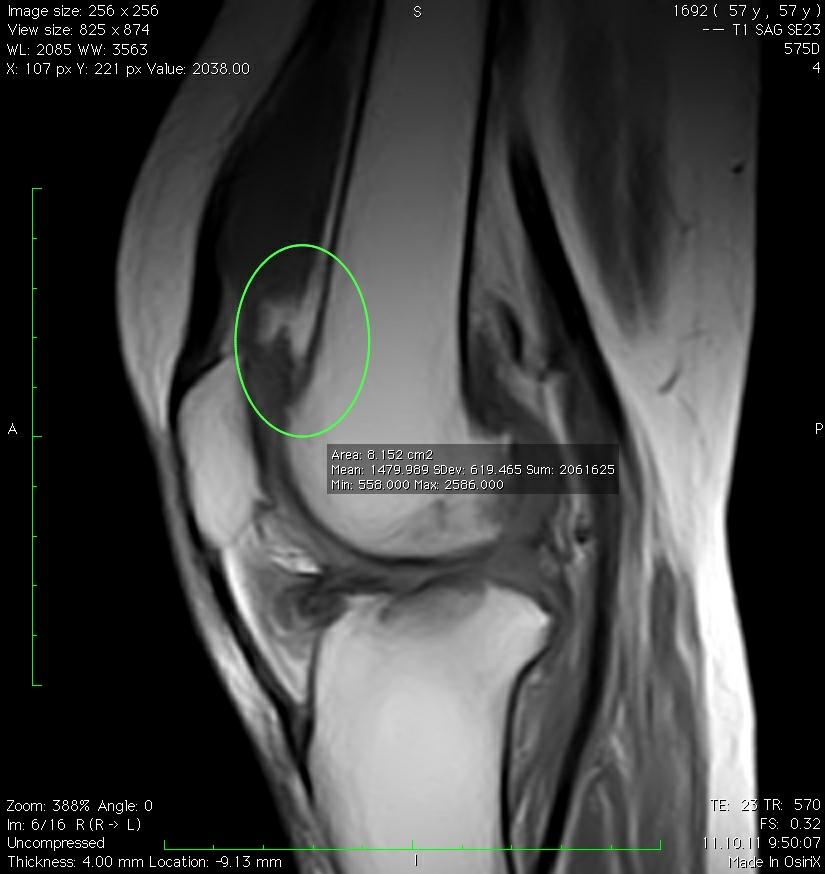

Супрапателлярный импиджмент коленного сустава: симптомы и лечение